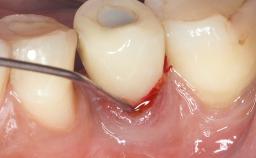

Surgical Treatment of Peri-Implantitis in the Posterior Mandible Associated with Hard- and Soft-Tissue Reconstruction

Paolo Casentini demonstrates that peri-implantitis can be successfully treated even at an advanced stage. He discusses a case in which the existing implants and prostheses were both retained while regenerating the defect and creating a band of keratinized tissue. A 69-year-old female patient was referred by her general dentist for evaluation of a recurrent infection at previously placed and restored implants in the posterior left mandible. The patient’s chief complaint was recurrent swelling and pain in the molar region of the left posterior mandible with discomfort during brushing in the same area. The patient reported receiving two implants (36 and 37) nine years earlier.